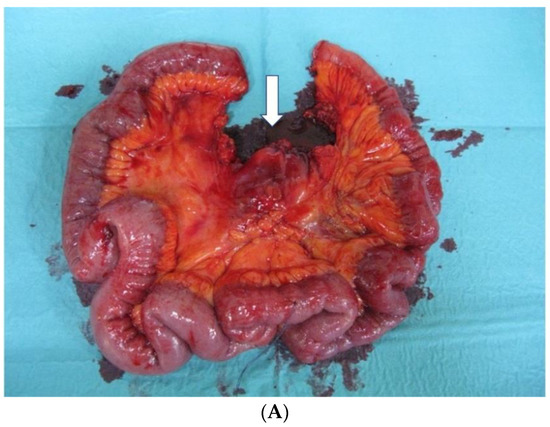

Figure 3.

(A) Small bowel specimen after Con-LA: arrow—lymph node metastases level 2. (B) Situs after VS-LA. D—duodenum; ICA—ileocolic artery; SMA—superior mesenteric artery.